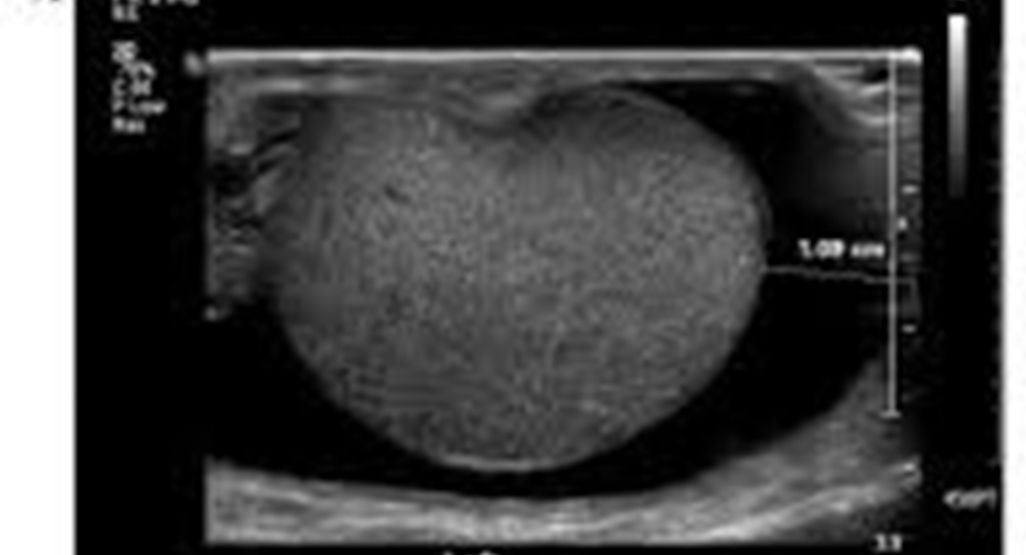

Evaluates the size and structure of the thyroid gland. Helps detect nodules, swelling, or thyroid disorders.

Examines breast tissue for lumps or abnormalities. Often used alongside mammography for accurate evaluation.

Evaluates testes and surrounding structures. Helps diagnose pain, swelling, or fertility-related issues.